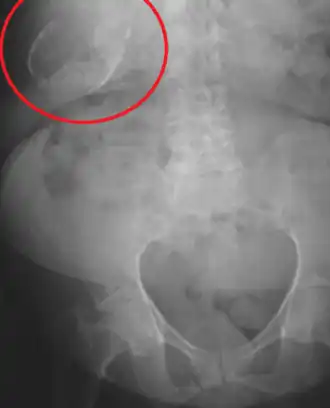

Vesícula biliar de porcelana

| Vesícula biliar de porcelana no raio-X | |

A vesícula biliar de porcelana é uma calcificação da vesícula biliar acreditada ser causada pelos cálculos biliares excessivos, embora a causa exata não esteja clara. Como na doença de cálculo biliar em geral, esta condição ocorre predominantemente em pacientes femininas de meia-idade com sobrepreso. É uma variante morfológica da colecistite crônica. A cicatrização inflamatória da parede, combinada à calcificação distrófica dentro da parede transforma a vesícula biliar em um vaso assemelhado à porcelana.

Radiografia abdominal (raio-X), ultrassom abdominal ou tomografia computadorizada.